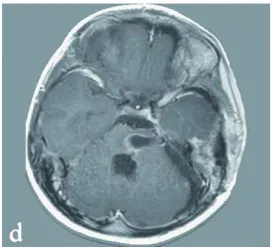

核磁共振检查结果发现:那位毫无症状的妈妈,大脑里其实也生长了多个海绵状血管畸形的小病灶,而爸爸的检查结果则完全正常。

图2,a,b:27岁无症状母亲的多发幕上海绵状血管瘤,呈典型低信号。c常规T2加权磁共振扫描:可见无症状母亲左额叶最大海绵状血管瘤(白色箭头)。

对其无症状双亲进行的基因检测和磁共振成像检查显示,27岁的母亲携带相同的基因突变并存在多发性海绵状血管瘤(图2)。因此,这位最初被认为是散发病例的患者,现可归类为家族性CCM。